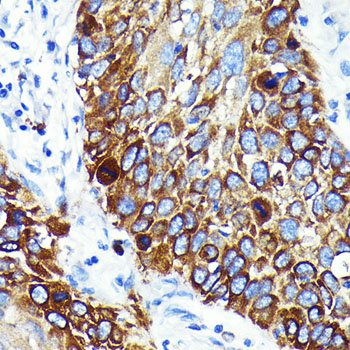

This gene encodes a member of the C1 family of peptidases. Alternative splicing of this gene results in multiple transcript variants. At least one of these variants encodes a preproprotein that is proteolytically processed to generate multiple protein products. These products include the cathepsin B light and heavy chains, which can dimerize to form the double chain form of the enzyme. This enzyme is a lysosomal cysteine protease with both endopeptidase and exopeptidase activity that may play a role in protein turnover. It is also known as amyloid precursor protein secretase and is involved in the proteolytic processing of amyloid precursor protein (APP). Incomplete proteolytic processing of APP has been suggested to be a causative factor in Alzheimer's disease, the most common cause of dementia. Overexpression of the encoded protein has been associated with esophageal adenocarcinoma and other tumors. Both Cathepsin B and Cathepsin L are involved in the cleavage of the spike protein from the severe acute respiratory syndrome coronavirus 2 (SARS-CoV-2) upon its entry to the human host cell. Multiple pseudogenes of this gene have been identified.